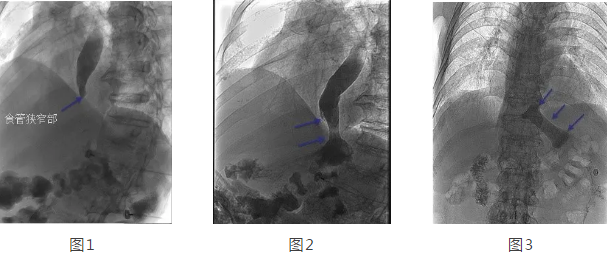

在韓國(guó)宏教授的帶領(lǐng)下,專(zhuān)家團(tuán)隊(duì)經(jīng)多方面評(píng)估后,決定在DSA下為劉大爺行食管造影 食管支架置入術(shù)。術(shù)中透視可見(jiàn)食管中上段擴(kuò)張明顯,食管下端賁門(mén)口明顯狹窄,造影劑淤積,呈線性緩慢進(jìn)入胃腔(見(jiàn)圖1),經(jīng)過(guò)準(zhǔn)確定位后,釋放食管支架,再次造影可見(jiàn)造影劑經(jīng)支架順利進(jìn)入胃腔(見(jiàn)圖2)。2天后再次造影見(jiàn)食管支架完全打開(kāi),位置正常,造影劑可順利通過(guò)支架(見(jiàn)圖3)。